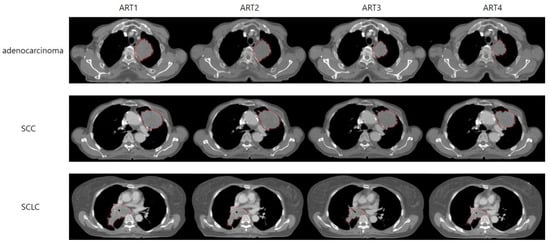

2.3. Imaging Acquisition and Registration Process

3.3. GTV Changes

3.3.1. Weekly Stepwise Tracking of GTV Changes: A Cumulative Comparison from the Start of Treatment